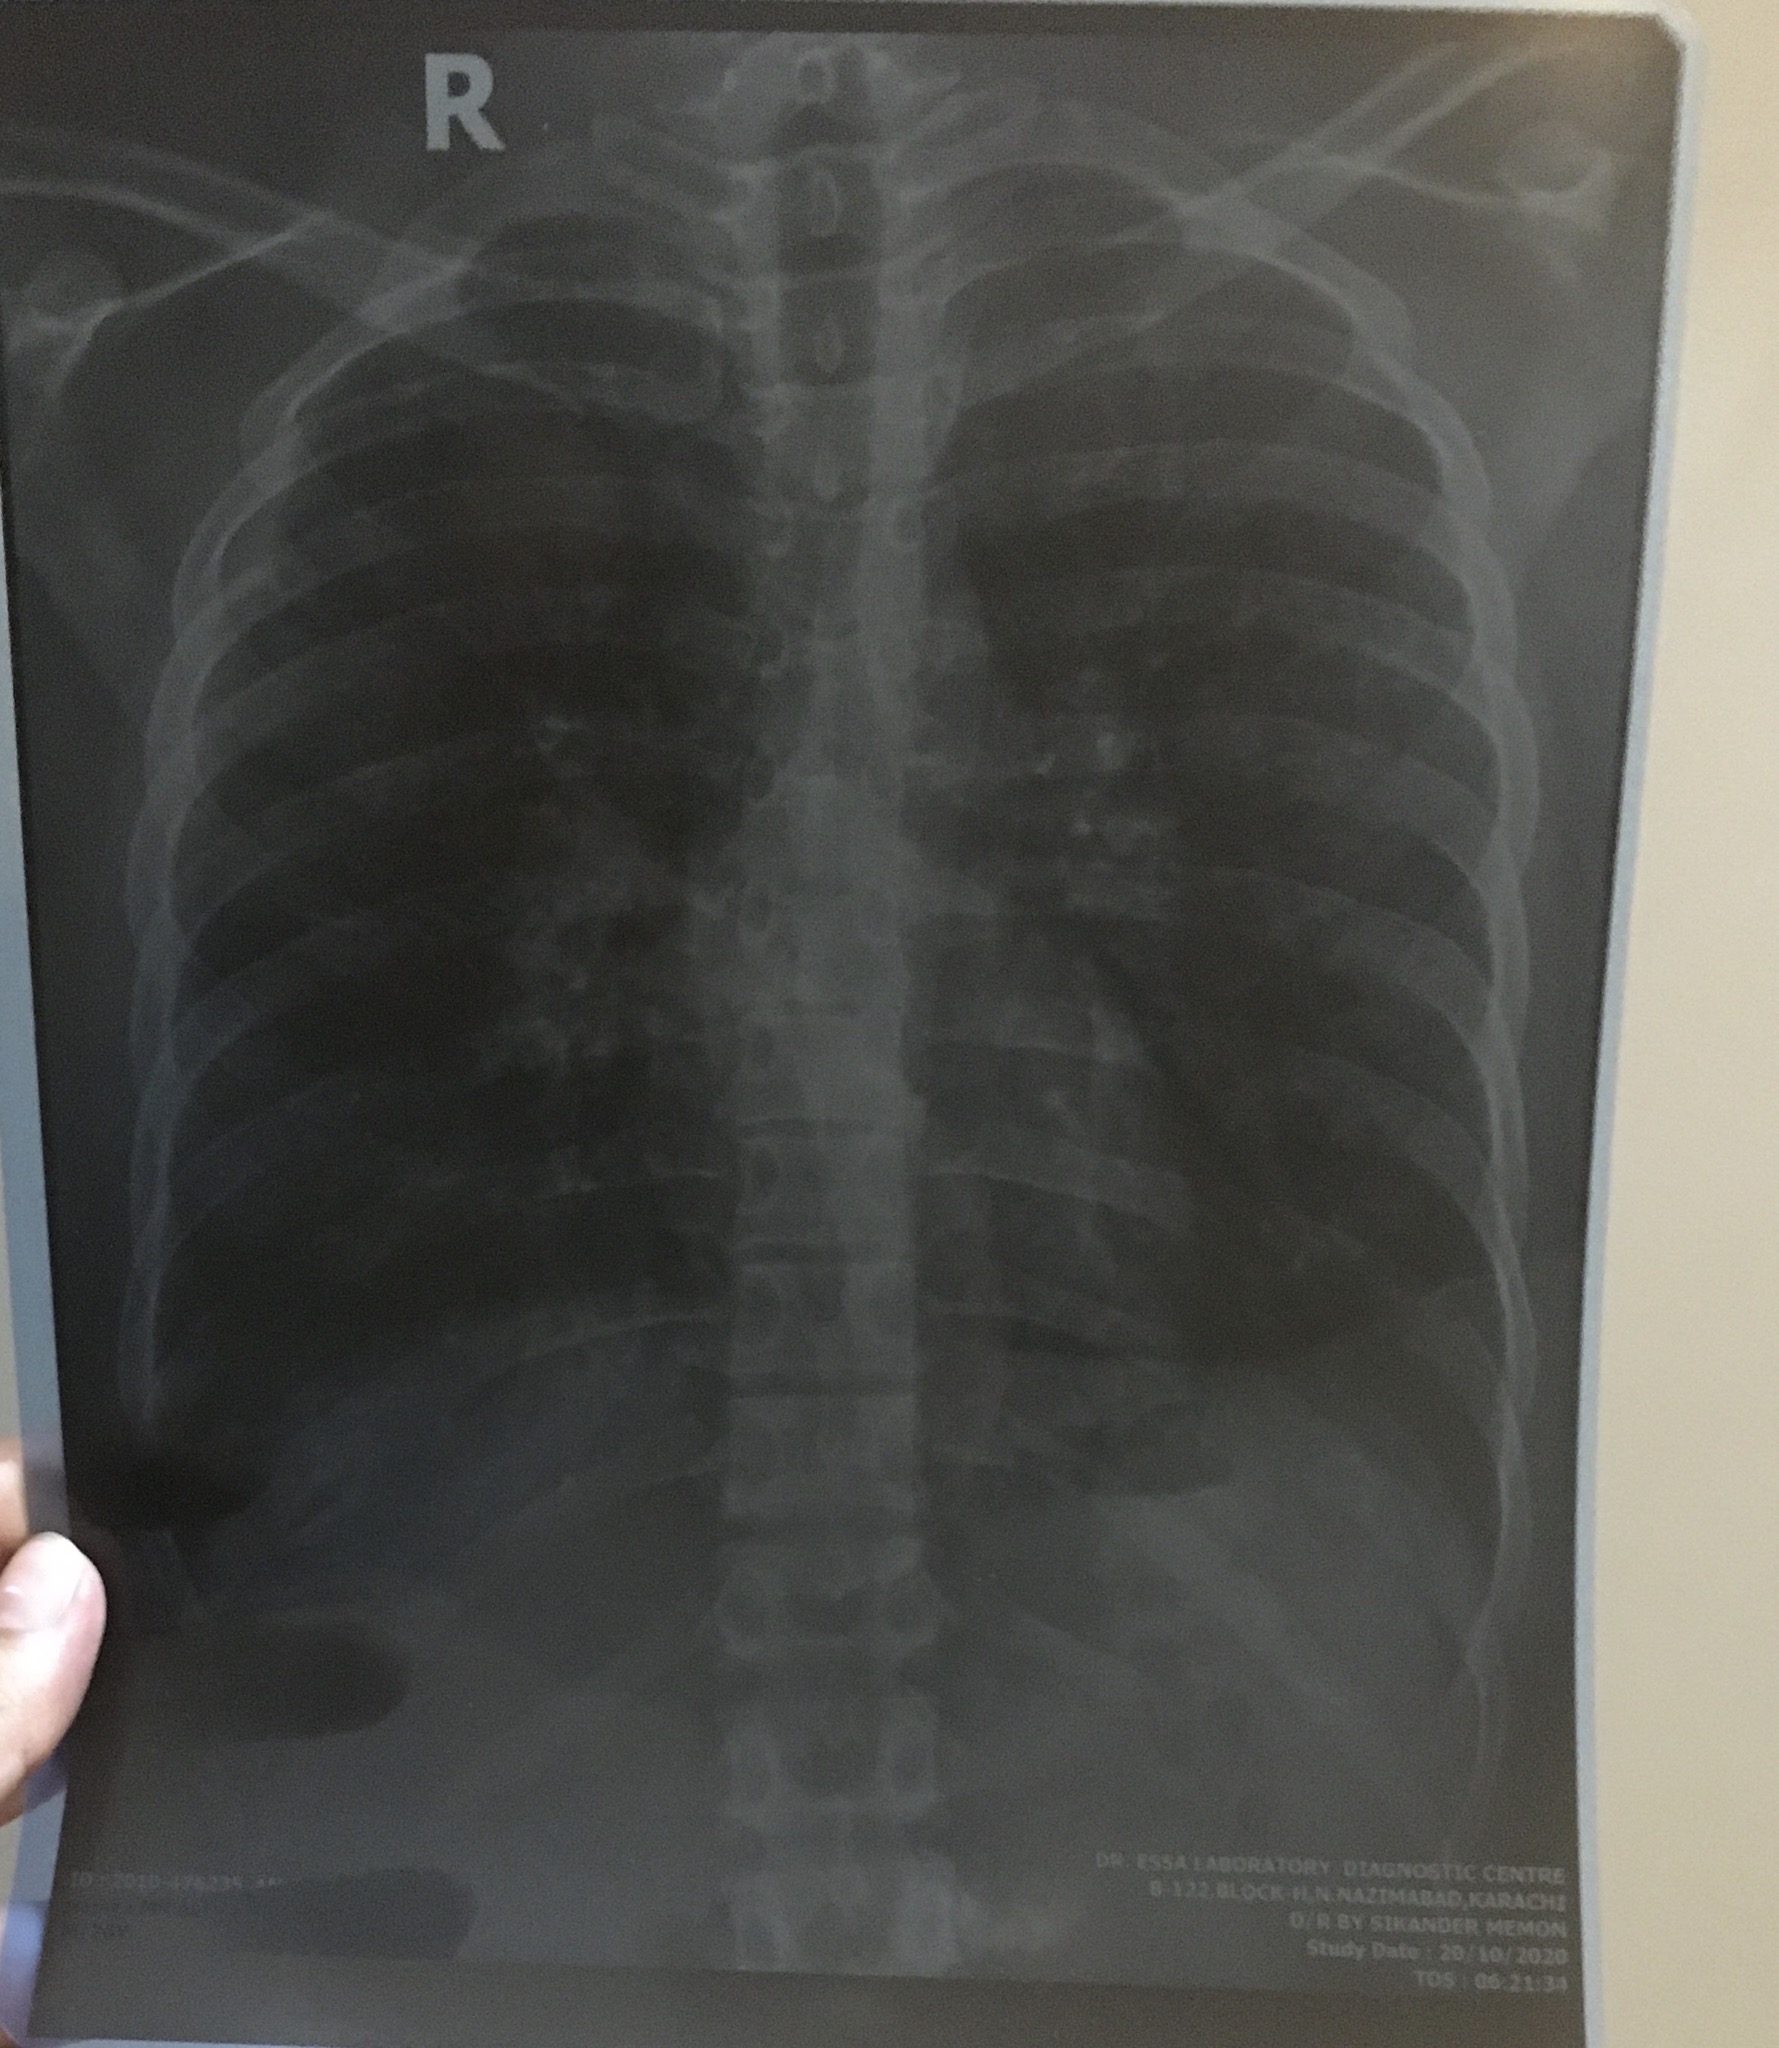

Asking for Husband, Male, 27 years old, Karachi

My husband’s reports are alarming can u plz tell if its actually lymphoma? No symptoms so far

this report only means that both hila of lung enlarge . your husband needs detailed examination and history with further evaluation by CT , bronchiscopy if needed, so plz visit chest physician

Sorry X-ray is too dark to make any report isn’t to have CT scan chest with contrast.

There are calcifications in lungs .To establish a diagnosis he needs to under go few more tests like sputum for AFB and Gene xpert MTB .Monitor his temperature .Is there past history of Pulmonary Tuberculosis ?

Okay i will note this temperature. He has zero symptoms and no fever! He’s scared about me because i am full term pregnant living with him. Am i at risk?

U r not at risk dear

Well for more detail clarification need CT scan chest for these suspected diagnosis.

CT chest with contrast is adviced